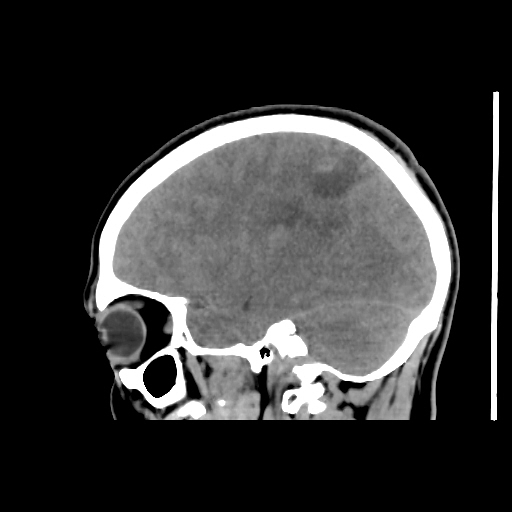

A 35 years old man CT head